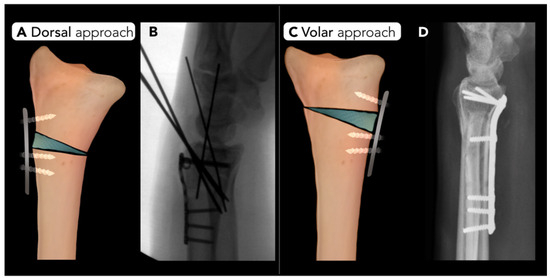

2.2.3. Distal Radius Corrective Osteotomy

- Evans, B.T.; Jupiter, J.B. Best approaches in distal radius fracture malunions. Curr. Rev. Musculoskelet. Med. 2019, 12, 198–203. [Google Scholar] [CrossRef] [PubMed]

- de Muinck Keizer, R.; Lechner, K.; Mulders, M.; Schep, N.; Eygendaal, D.; Goslings, J. Three-dimensional virtual planning of corrective osteotomies of distal radius malunions: A systematic review and meta-analysis. Strateg. Trauma Limb Reconstr. 2017, 12, 77–89. [Google Scholar]

- Peterson, B.; Gajendran, V.; Szabo, R.M. Corrective osteotomy for deformity of the distal radius using a volar locking plate. Hand 2008, 3, 61–68. [Google Scholar] [CrossRef]

- Haines, S.C.; Bott, A. Current Concepts: Corrective Osteotomy for Extra-Articular Deformity Following a Distal Radius Fracture. Cureus 2023, 15, e47019. [Google Scholar] [CrossRef]